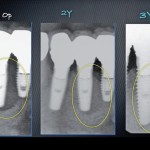

Questo studio prospettico, controllato e randomizzato intende valutare sopravvivenza e successo di 270 impianti a connessione conometrica, a sostegno di corone singole, inseriti nei...